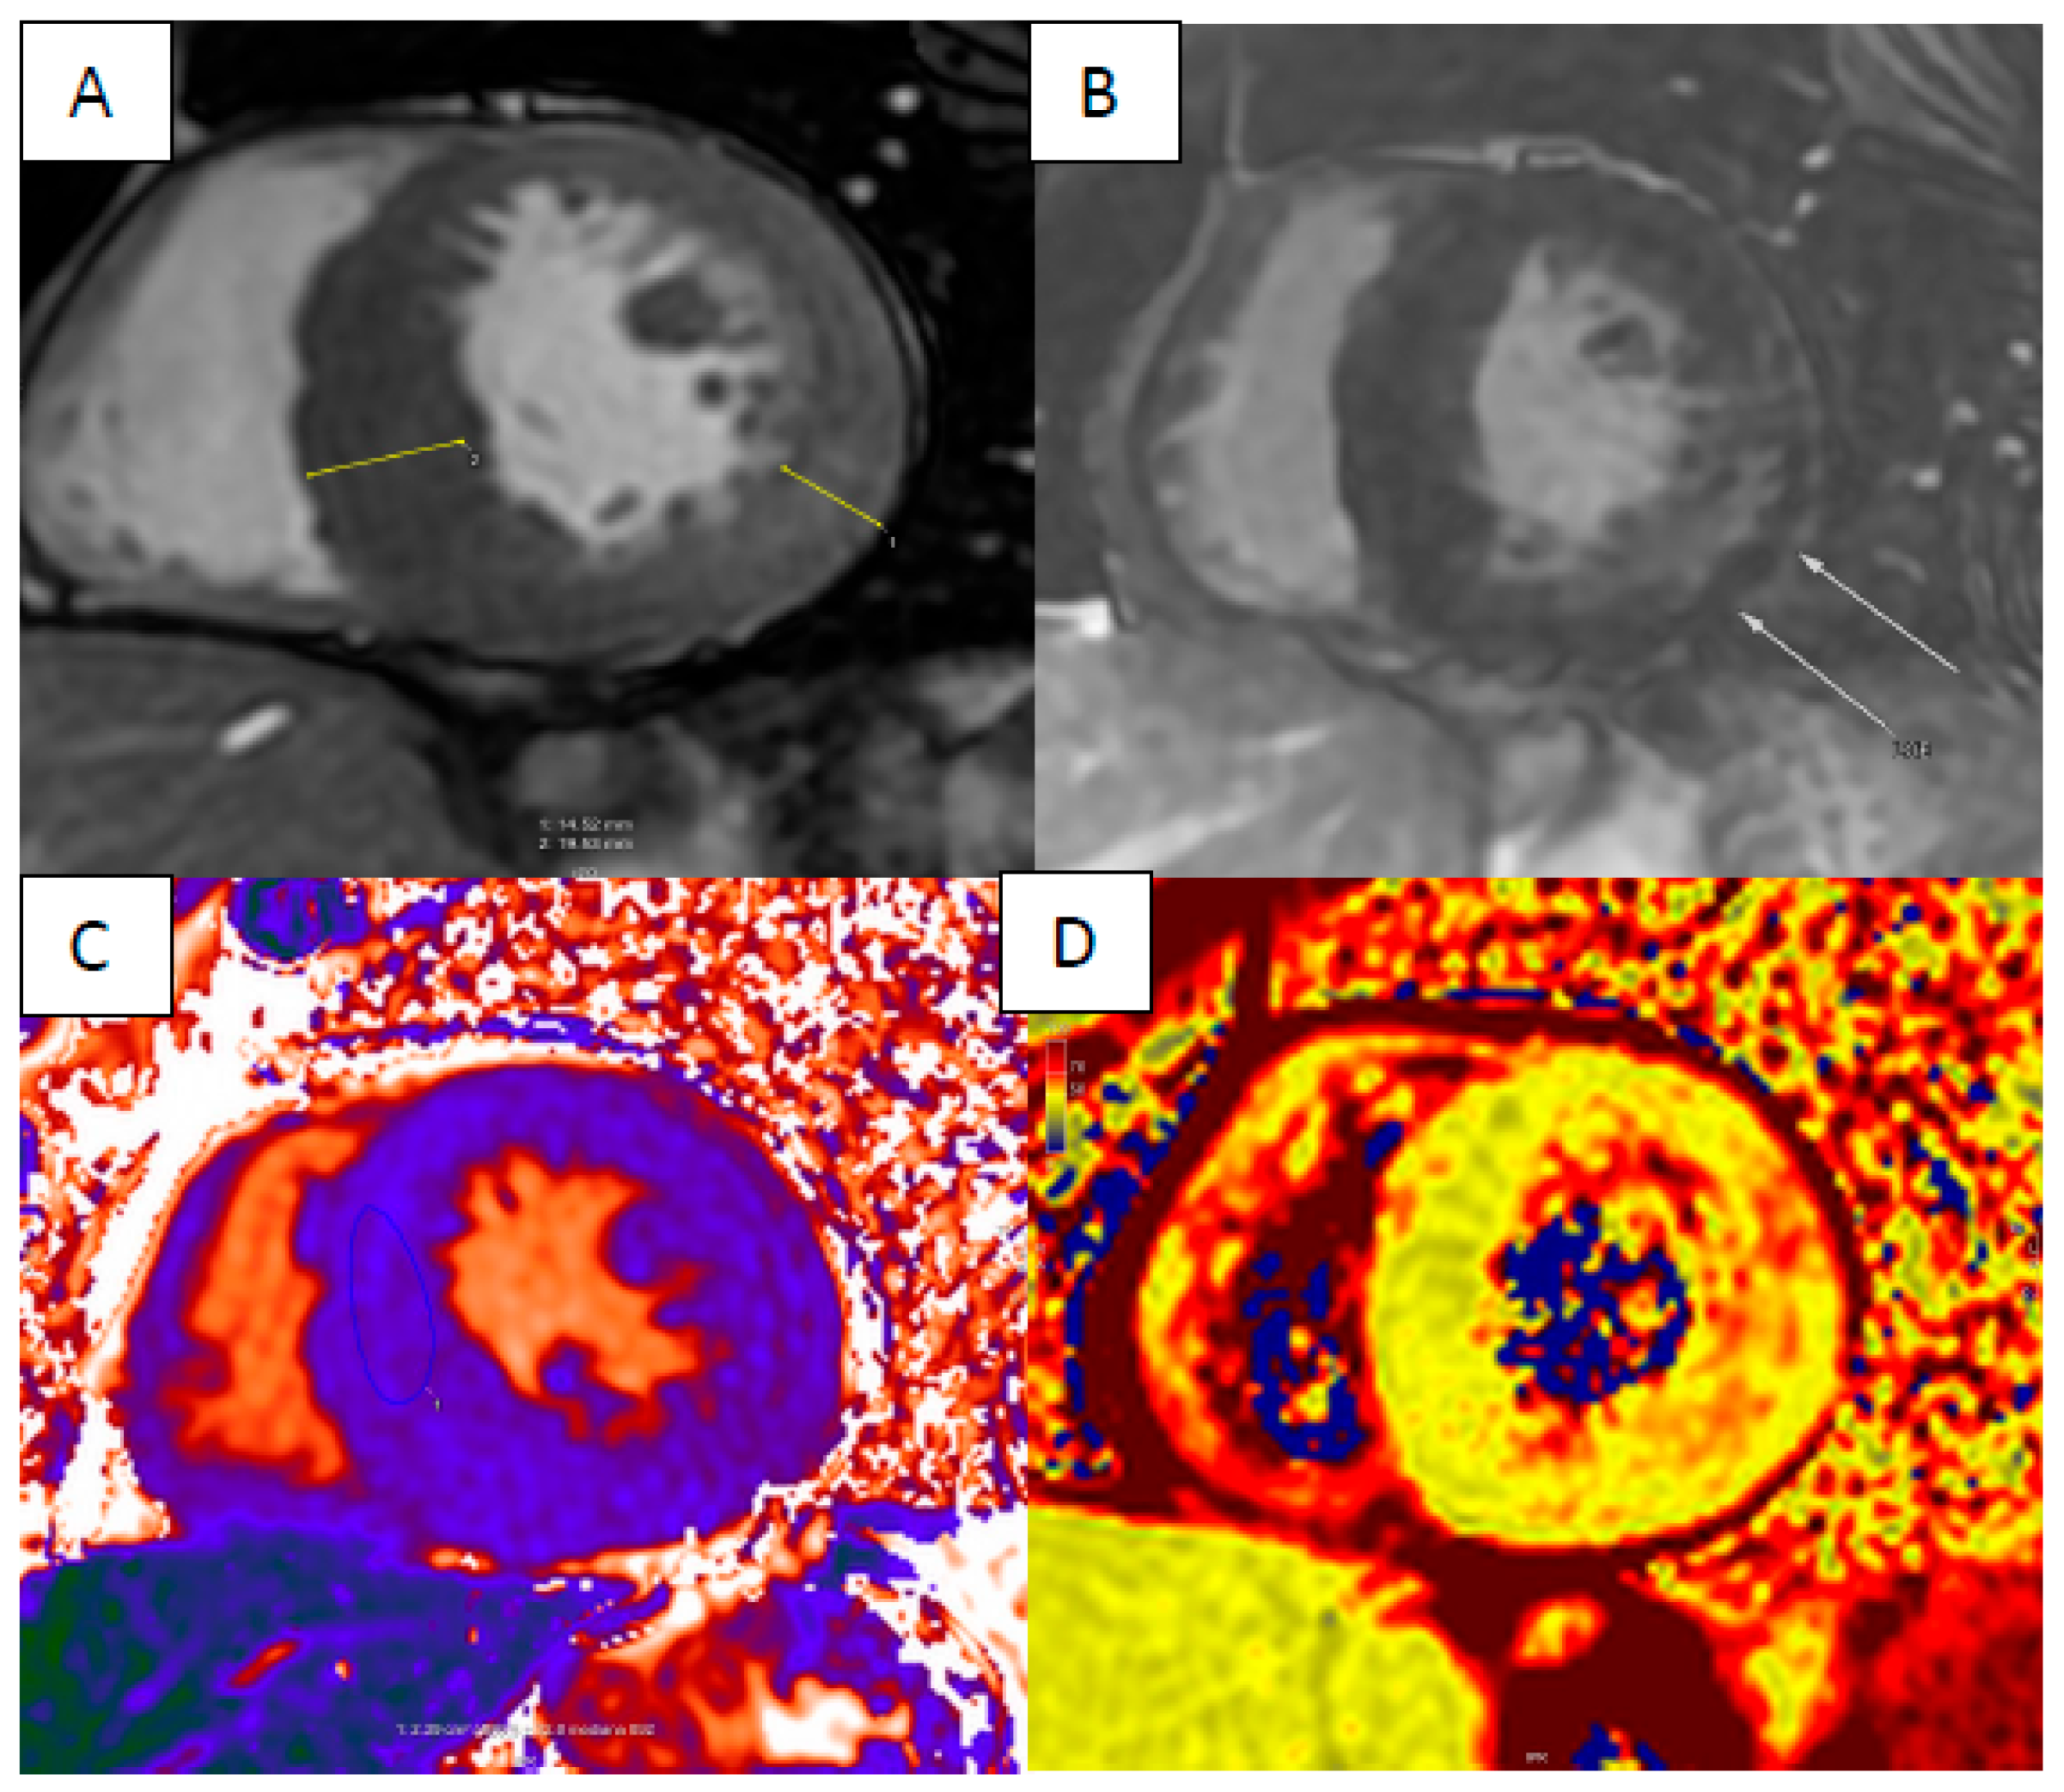

4. Cardiac Amyloidosis

5. Anderson–Fabry Disease